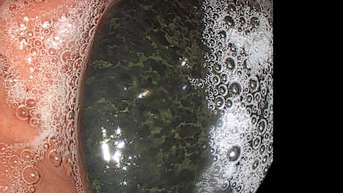

위장관 상피하 종양 및 아칼라시아 치료의 진전

AI 기술로 암 조기 손상 감지해 암 위험 예방

무통, 비감염 소화기내시경